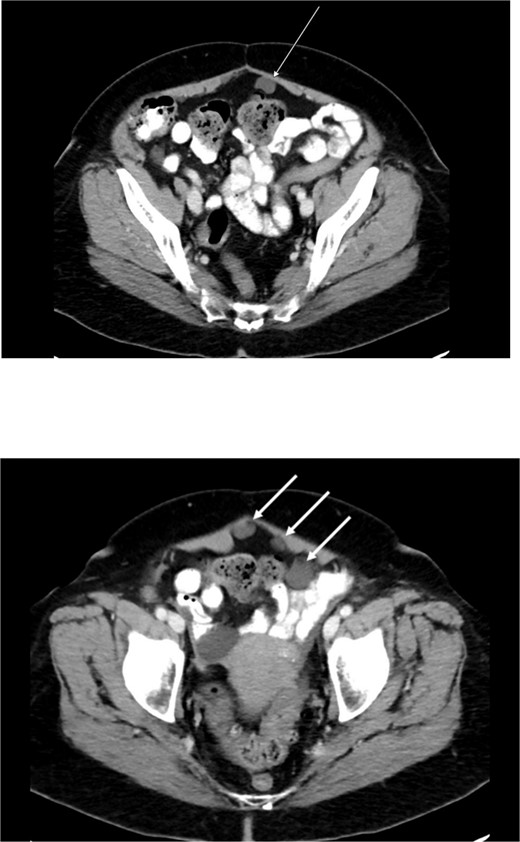

Diagnostic laparoscopy demonstrated multiple cystic lesions throughout the abdomen and pelvis (Figs 3 and 4). The gross appearance of these cysts was consistent with mucinous carcinomatosis. Laparoscopic excisional biopsy of several lesions was performed. Frozen section analysis revealed mucin but did not reveal evidence of metastatic adenocarcinoma. Colectomy was deferred due to concern for carcinomatosis, as if confirmed, she would likely be treated with neoadjuvant chemotherapy, restaging, followed by cytoreductive surgery (to include synchronous right colectomy) with heated intraperitoneal chemotherapy.

Intraoperative view of the right lower quadrant of the abdomen: cysts involving peritoneum of the right colon and mesentery.